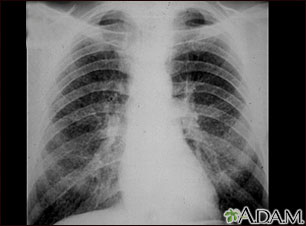

A chest x-ray is an x-ray of the chest, lungs, heart, large arteries, ribs, and diaphragm.

How the Test is Performed

You stand in front of the x-ray machine. You will be told to take a breath in and hold it when the x-ray is taken.

Two images are usually taken. You will first need to stand facing the machine, and then sideways.